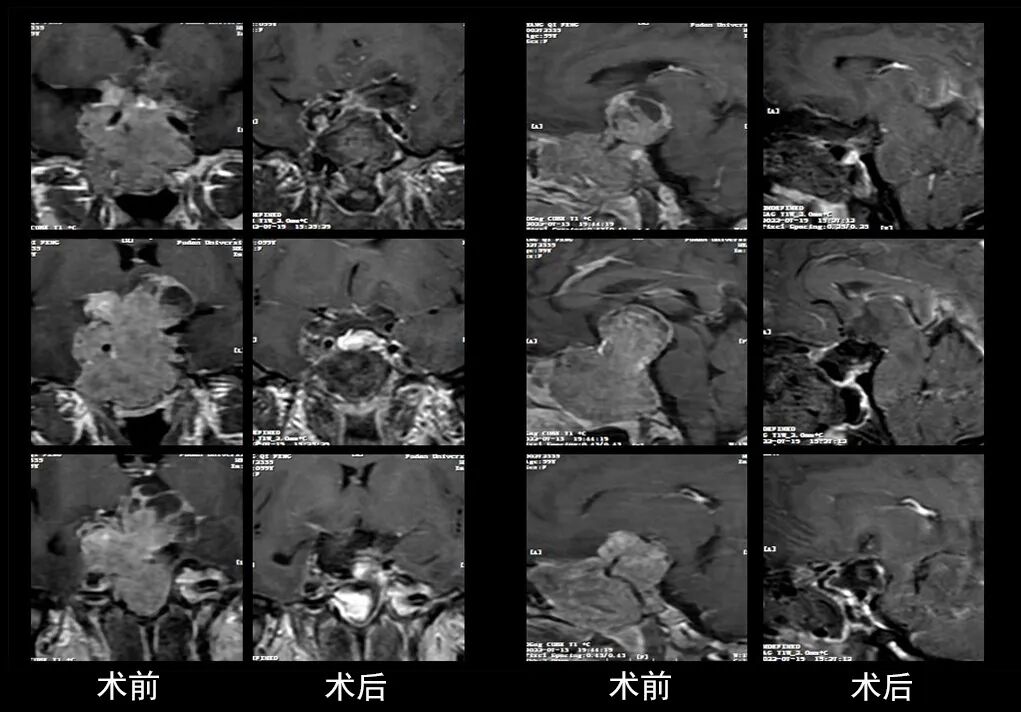

本研究中采用联合手术策略的代表性病例展示:

case 5

case 6